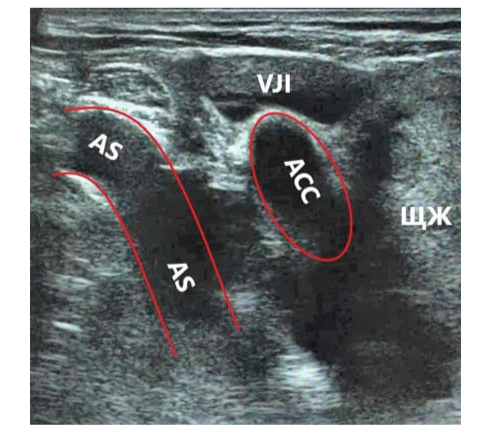

УЗИ выполнялось пациентам в положении лежа на спине с валиком под лопатками и ротацией головы влево. УЗИ проводилось в В-режиме и режиме цветного допплеровского картирования. Методика заключалась в прослеживании хода правой общей сонной артерии до брахиоцефального ствола (БЦС) и выявлении Y-признака (область бифуркации БЦС на правую подключичную и общую сонную артерии при УЗИ выявлялась в виде Y-образной структуры) (рис. 1). При отсутствии подобной структуры правая общая сонная артерия прослеживалась максимально низко по возможности до дуги аорты. Далее визуализировалась правая подключичная артерия и оценивались ее ход и синтопия с правой общей сонной артерией, трахеей.

Рис. 1. УЗИ сосудов шеи (цветное дуплексное сканирование). Выявление Y-признака. ACC – arteria carotis communis dexter, AS – arteria subclavia dexter, TBC – truncus brachiocephalicus.

По данным предоперационного УЗИ у 202 (95,28%) пациентов определялся БЦС с бифуркацией на правую подключичную и общую сонную артерии в виде Y-образной структуры (рис. 1).

Рис. 6. УЗИ сосудистого пучка правой половины шеи линейным датчиком на уровне грудино-ключичного сочленения. Отсутствие Y-признака. Правая общая сонная и правая подключичная артерии располагаются близко и практически параллельно друг другу. БЦС располагается низко в средостении и визуализации не доступен. ЩЖ – узел правой доли ЩЖ с частичным загрудинным расположением. ACC – arteria carotis communis dexter, VJI – vena jugularis interna dexter, AS – arteria subclavia dexter.